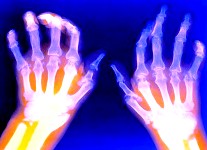

Impresionante avance para el futuro del tratamiento de la artritis

Estudio dice que es posible la regeneración de articulaciones con celulas madre.

Los científicos ya han regenerado con éxito las articulaciones de las extremidades de animales con células madre, dando así una esperanza a los pacientes con artritis y articulaciones que necesitan reemplazarse.